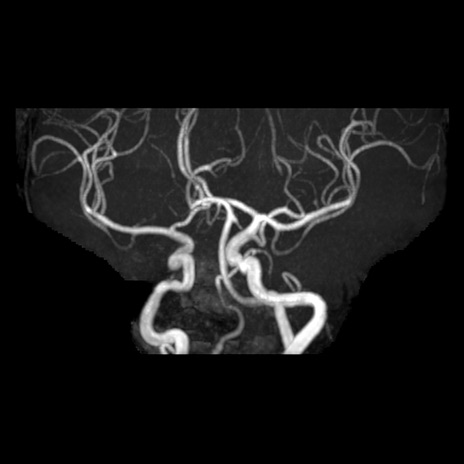

【頭部MRA】症例9 MRA MIP像

【症例】60歳代女性

どんな血管の正常変異がありますか?